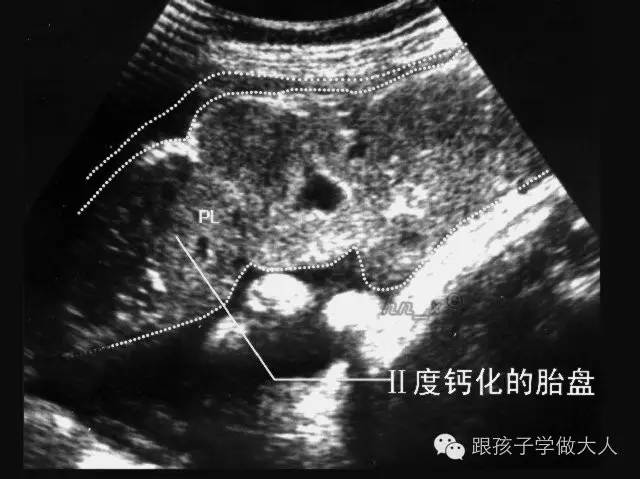

胎盘是有一定寿命的,预产期过后的两周,胎盘的功能开始减退,造成输氧不足,使胎儿经常处于缺氧状态。过期妊娠的胎盘,在胎儿娩出时常比正常胎盘要小,表面散有白色斑纹,有时还可以看到坚硬如石的钙化点,这就是胎盘老化的症状。